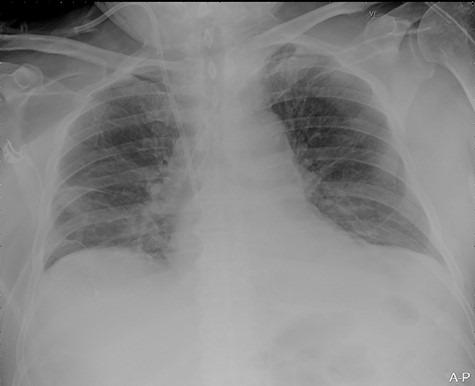

A 74-year-old male patient with a history of type 2 diabetes mellitus, ankylosing spondylitis and cystoprostatectomy with Bricker bladder was admitted with acute renal failure not responding to conservative measures. He needed haemodialysis. Due to clinical deterioration with dyspnoea, hypotension and inadequate peripheral perfusion during intermittent haemodialysis, he was transferred to the intensive care unit (ICU). A right-sided pleural effusion was found, and the intensivist inserted a pigtail pleural drain under ultrasound guidance. The fluid was somewhat bloody, but control with ultrasound and CXR (Fig. 1) after the procedure was normal.

Portable chest X-ray with no pleural effusion after placement of pigtail pleural drain.